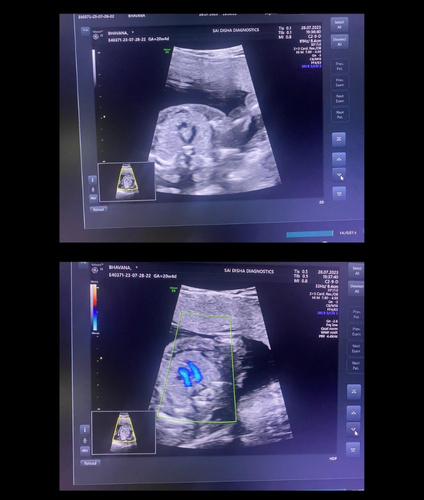

An ultrasound scan, also known as sonography, is a safe and non-invasive diagnostic procedure that uses sound waves to produce real-time images of the inside of the body. Unlike X-rays or CT scans, ultrasound does not use any radiation, making it especially suitable for monitoring pregnancies and for routine diagnostic imaging. During the procedure, a special gel is applied to the skin, and a device called a transducer is gently moved over the area of interest. The sound waves travel into the body and bounce back to create clear images of organs, tissues, and blood flow and fetus inside pregant mother.

Sai Disha Diagnostics offers high-resolution ultrasound imaging to support early and precise diagnosis across a wide range of medical conditions.

We offer pregnancy, abdominal, pelvic, thyroid, breast, and Doppler ultrasound scans.